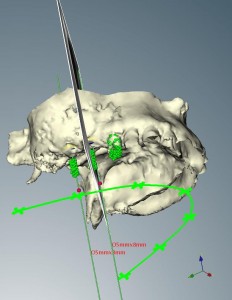

インプラントコンピュータシミュレーション。

インプラント治療を行う場合、全身状態やかみ合わせなどのお口の中の状態などの診査の他に、インプラントを入れる顎骨の状態を正確に知ることは、手術を成功に導くために最も重要な要因となります。

今から10年以上前は歯科用CTもまだあまり普及していませんでしたので、通常のレントゲンのみで手術を行っている時代もありました。

その後、CTにより3次元的に顎骨の状態を把握できるようになり、4~5年前まではただ診断に用いるのみでしたが、

現在ではCTで撮影した顎骨のデータを専用のソフト(ノーベルガイド)で解析し、手術用のガイドを製作出来るようになりました。

手術用のガイドを用いることにより、事前に診断し決定した位置や方向に、正確かつ早く、安全にインプラントを入れていくことが可能です。

インプラントは日々進歩しています。